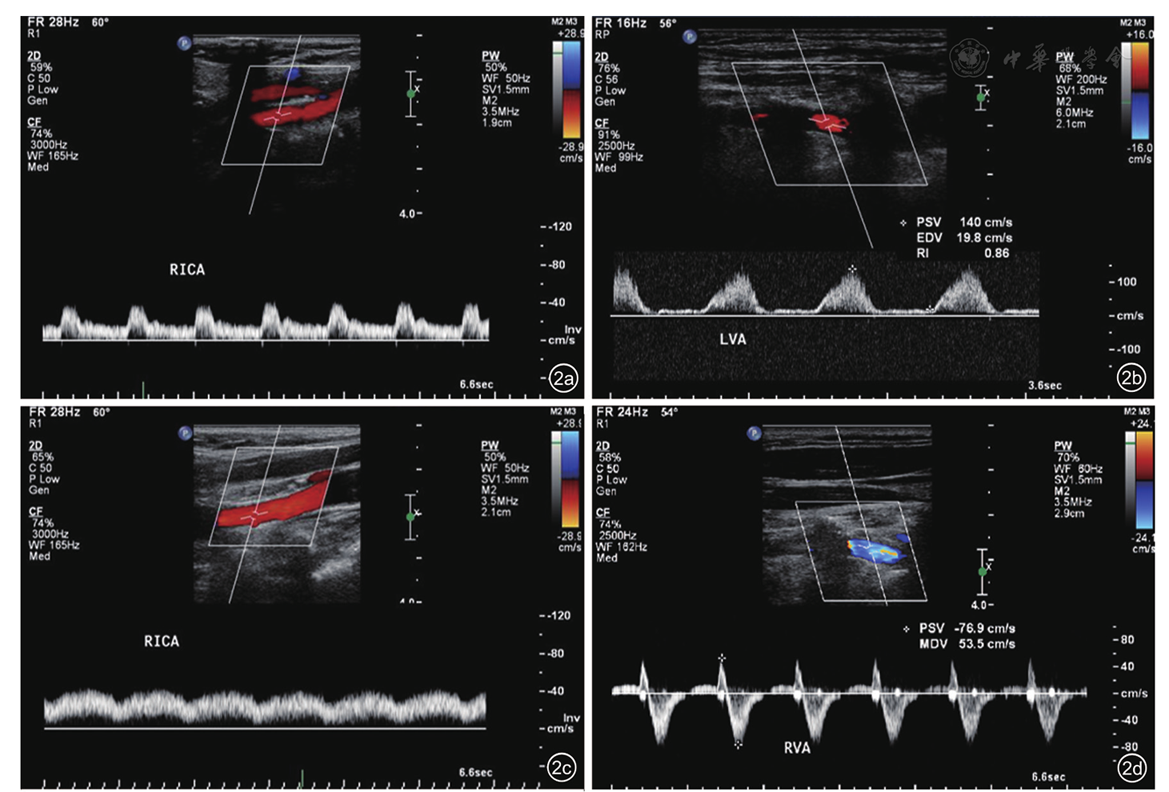

图2 颈部动脉夹层患者的不同类型颈部动脉血流频谱图像。图a为正常频谱;图b为高阻力频谱;图c为低速低阻频谱;图d为窃血频谱